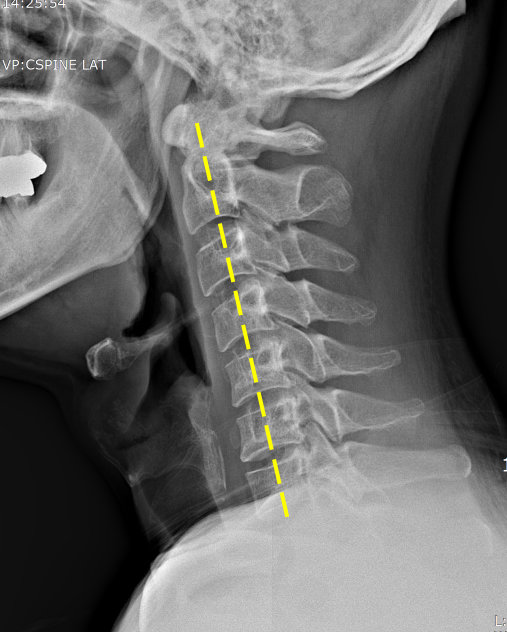

척추에는 뼈의 정렬과 움직임 그리고 안정감을 담당하기 위함으로 지지대 역할을 하는 여러 인대가 존재해요. 전형적으로 척추 전방의 전종인대와 후방의 후종인대를 들 수 있어요. 척추는 목 부위의 경추부터 꼬리뼈 주위 천추에 이르는 33개의 뼈로 되어 있으며 척추관은 척추 가운데 관 형상의 빈 공간으로 척추관 속에는 뇌로부터 팔다리까지 신경이 지나가는 통로라고 할수 있습니다.